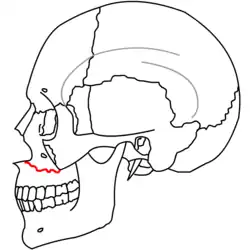

|

| Le Fort I fractures | |

At the beginning of the 20th century, René Le Fort mapped typical locations for facial fractures; these are now known as Le Fort I, II, and III fractures (right).[7] Le Fort I fractures, also called Guérin or horizontal maxillary fractures,[14] involve the maxilla, separating it from the palate.[15] Le Fort II fractures, also called pyramidal fractures of the maxilla,[16] cross the nasal bones and the orbital rim.[15] Le Fort III fractures, also called craniofacial disjunction and transverse facial fractures,[17] cross the front of the maxilla and involve the lacrimal bone, the lamina papyracea, and the orbital floor, and often involve the ethmoid bone,[15] are the most serious.[18] Le Fort fractures, which account for 10–20% of facial fractures, are often associated with other serious injuries.[15] Le Fort made his classifications based on work with cadaver skulls, and the classification system has been criticized as imprecise and simplistic since most midface fractures involve a combination of Le Fort fractures.[15] Although most facial fractures do not follow the patterns described by Le Fort precisely, the system is still used to categorize injuries.[5]